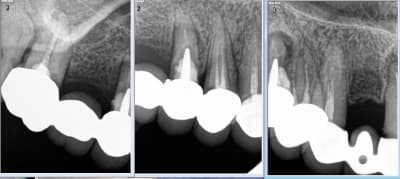

Ca te pousse à t'améliorer en fixe : t'évites de toucher la gencive pendant tes tailles : moins ca saigne mieux c'est.